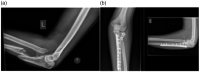

Background: Elbow fracture dislocations are complex injuries that can provide a challenge for experienced surgeons. Current classifications fail to provide a comprehensive system that encompasses all of the elements and patterns seen in elbow fracture dislocations.

Methods: The commonly used elbow fracture dislocation classifications are reviewed and the three-column concept of elbow fracture dislocation is described. This concept is applied to the currently recognised injury patterns and the literature on management algorithms.

Results: Current elbow fracture dislocation classification systems only describe one element of the injury, or only include one pattern of elbow fracture dislocation. A new comprehensive classification system based on the three-column concept of elbow fracture dislocation is presented with a suggested algorithm for managing each injury pattern.

Discussion: The three-column concept may improve understanding of injury patterns and treatment and leads to a comprehensive classification of elbow fracture dislocations with algorithms to guide treatment.